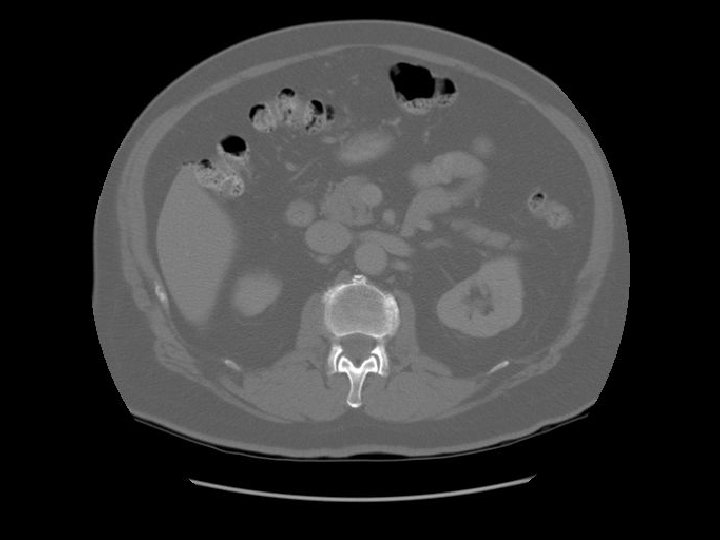

Transverse colon Ileum

Kidney Right Kidney

Descending colon Right

Renal pelvis

Ascending colon Right colon with fecal material.

Abdominal aorta about to bifurcate.

Psoas